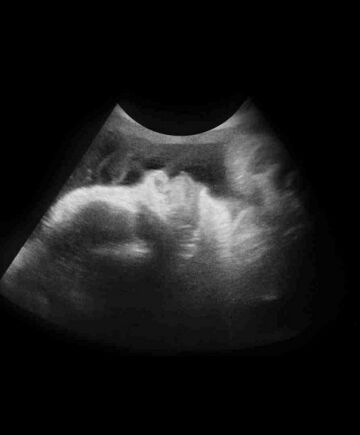

恭喜!你的胎儿从一个小细胞发育到2亿个细胞。40周出生的宝宝平均体重在3.3~4千克左右,身长大概有51厘米。

胎儿内脏和神经系统功能已经健全,手脚肌肉发达,富有活力,脑细胞的发育基本定型。胎儿的胸部会变得更凸出,由于肝在血红细胞生产中的特殊作用,胎儿的肝会自然变大。

别指望刚生出来的宝宝像洋娃娃那么可爱,新生儿头部通常都是暂时的畸形(通过产道时挤压所致),浑身覆盖着胎脂和血液,还可能肤色不匀,有胎记或皮疹,这些现象都是正常的。